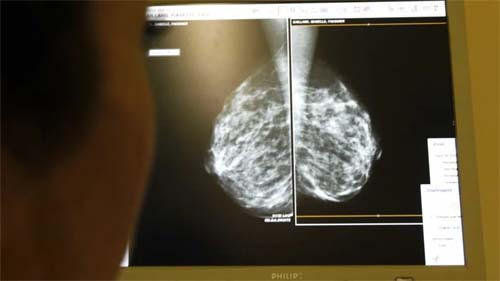

Fora do trato digestório, o câncer que mais mata no país é o de pulmão e de outros órgãos do sistema respiratório, com 22.853 mortes registradas ao longo do ano. A incidência varia conforme o gênero: entre as mulheres, o câncer de mama é o mais comum; já entre os homens, o de próstata ocupa o primeiro lugar.